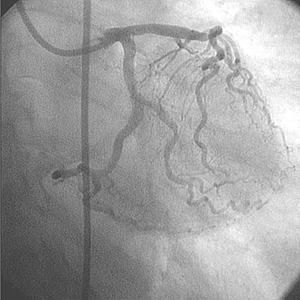

Tratamiento de la circunfleja

• Se colocó un catéter guía adecuado para facilitar el posible uso de varios dispositivos intervencionistas.

• Se usó una cuerda guía para cruzar la lesión en la arteria circunfleja.

• Se intentó sin éxito la dilatación de la lesión con un balón de 4,0 mm × 20 mm.

• Se intentó sin éxito la dilatación de la lesión con balón de 4,0 mm × 15 mm a 14 ATM.

• Tampoco se obtuvo éxito en expandir la lesión con un balón de 4,0 mm × 20 mm a 14 ATM.

• Se utilizó balón de corte Flextome™ de 4,0 mm × 10 mm, sin éxito.